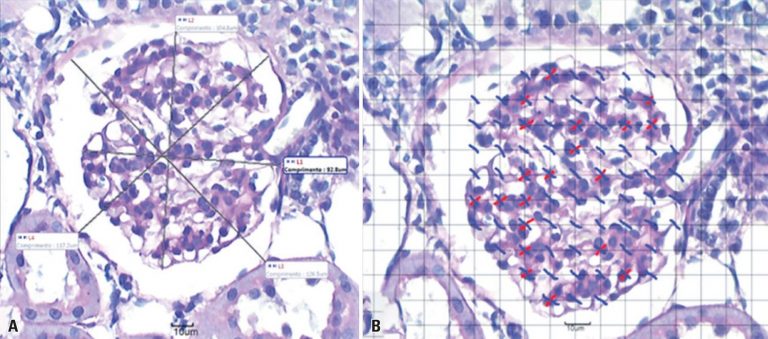

ABSTRACT Objective To analyze whether passive inhalation of cigarette smoke causes morphological, structural, and functional changes in kidneys of rats. Methods Wistar rats, aged eight weeks, weighing on average 260g, were divided into Control Group and Smoking Group. Each group was subdivided into four groups of ten animals for morphofunctional analysis, in a period of seven and 28 days. The Smoking Group was exposed to smoke of 40 cigarettes per day, at certain times and in automated equipment for cigarette […]

Keywords: Diabetic nephropathies; Glomerular filtration rate; Kidney cortex; Kidney glomerulus; Mesangial cells; Rats, Wistar; Tobacco smoke pollution